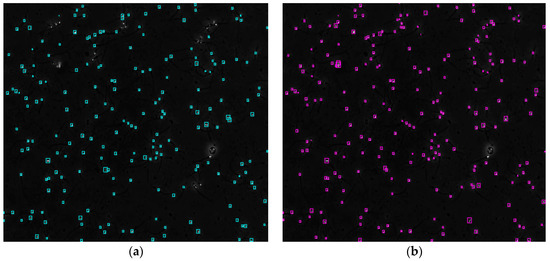

| Case | Conventional Image Processing | YOLOv3-spp | YOLOv5s | YOLOv5s-SA |

|---|---|---|---|---|

| 1 | ![]() | ![]() | ![]() | ![]() |

| 2 | ![]() | ![]() | ![]() | ![]() |